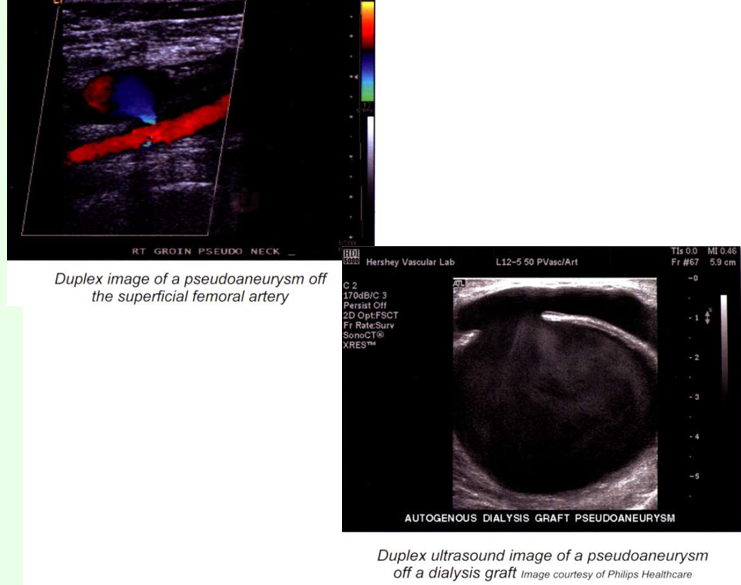

pseudoaneurysm